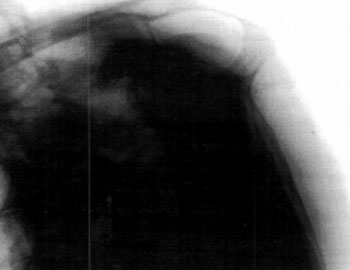

Figura IV:

Radiografía "Outlet View"

Es específica para evaluar el espacio subacromial. Se toma con 100 hacia abajo de la dirección del rayo, con la espína de la escápula paralela al piso.